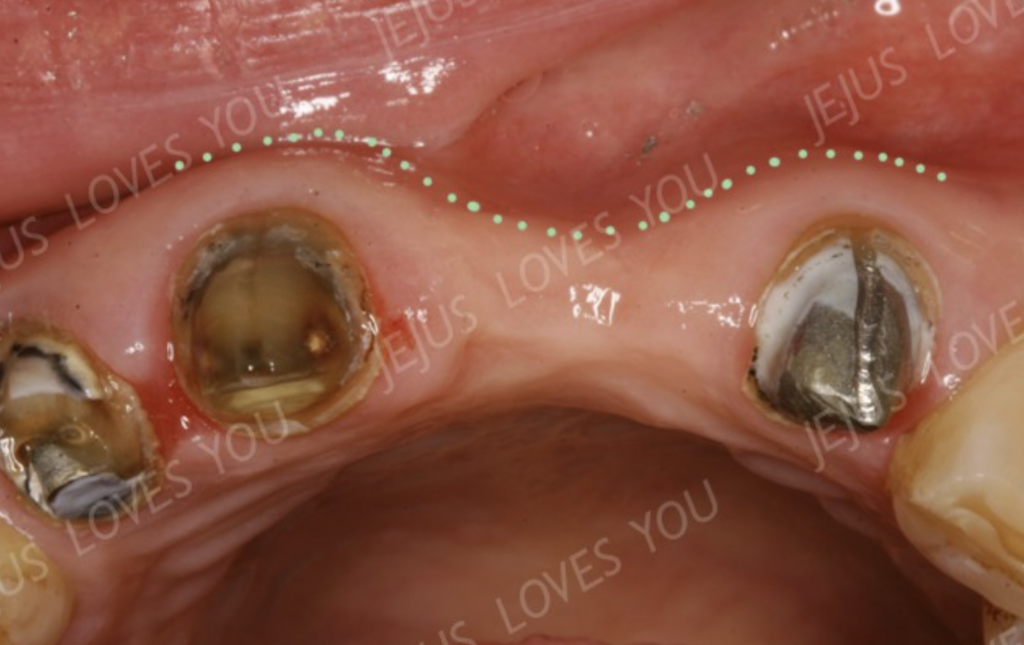

사진처럼 치아의 머리가 다 사라진 경우라도 뼈 속에 뿌리만 남아 있다면 뼈의 모양이 유지되고 있을 것을 볼 수 있습니다.

하지만 치아를 뽑고 그냥 방치하게 되면(즉, 브릿지나 메릴랜드, 휴먼브릿지 치료도 동일합니다.) 이렇게 시간이 지나면서 서서히 뼈가 얇아지게 되지요.